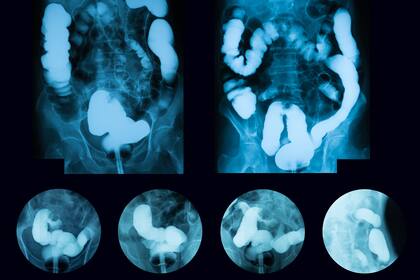

Es el enemigo público número dos dentro del universo de los tumores: cada año, el cáncer de colon causa unas 8721 muertes en el país. Es el segundo en mortalidad después del de pulmón. Sin embargo, tomado a tiempo es uno de los tumores más curables y prevenibles. Pero, debido a la pandemia, según advirtió hoy la Sociedad Argentina de Coloproctología (SACP), las consultas cayeron un 50% y se suspendió el 72% de las cirugías. Por esa razón, en los próximos años, los casos podrían aumentar.

El cáncer de colon es también el segundo en incidencia, después del cáncer de mama. Cada año, se detectan unos 15.692 nuevos casos.

En el caso de la detección de lesiones tumorales en el colon, la detección precoz es fundamental y mejora las chances del paciente. Algunos médicos explican que recién ahora están empezando a llegar las consultas que se postergaron en marzo o abril, por el comienzo de la pandemia, y el pronóstico en algunos casos es complicado.